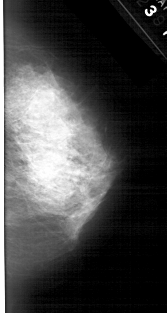

A_1474_1.LEFT_MLO

LEFT_MLO LINES 5491 PIXELS_PER_LINE 2761 BITS_PER_PIXEL 12 RESOLUTION 43.5 OVERLAY